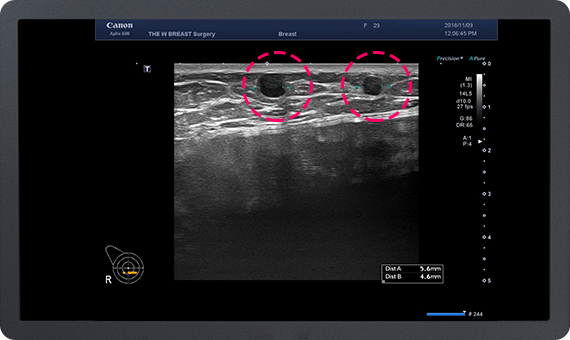

가슴지방 이식 수술 후 발생하는 가장 많은 부작용은

지방 낭종과 석회화입니다.

이에 대해 많은 경험을 가진 THE W 유방센터에서는

지방 이식 후 발생한 지방낭종과 석회화의 제거가 가능하며,

지속적인 유방암 추적이 가능합니다.